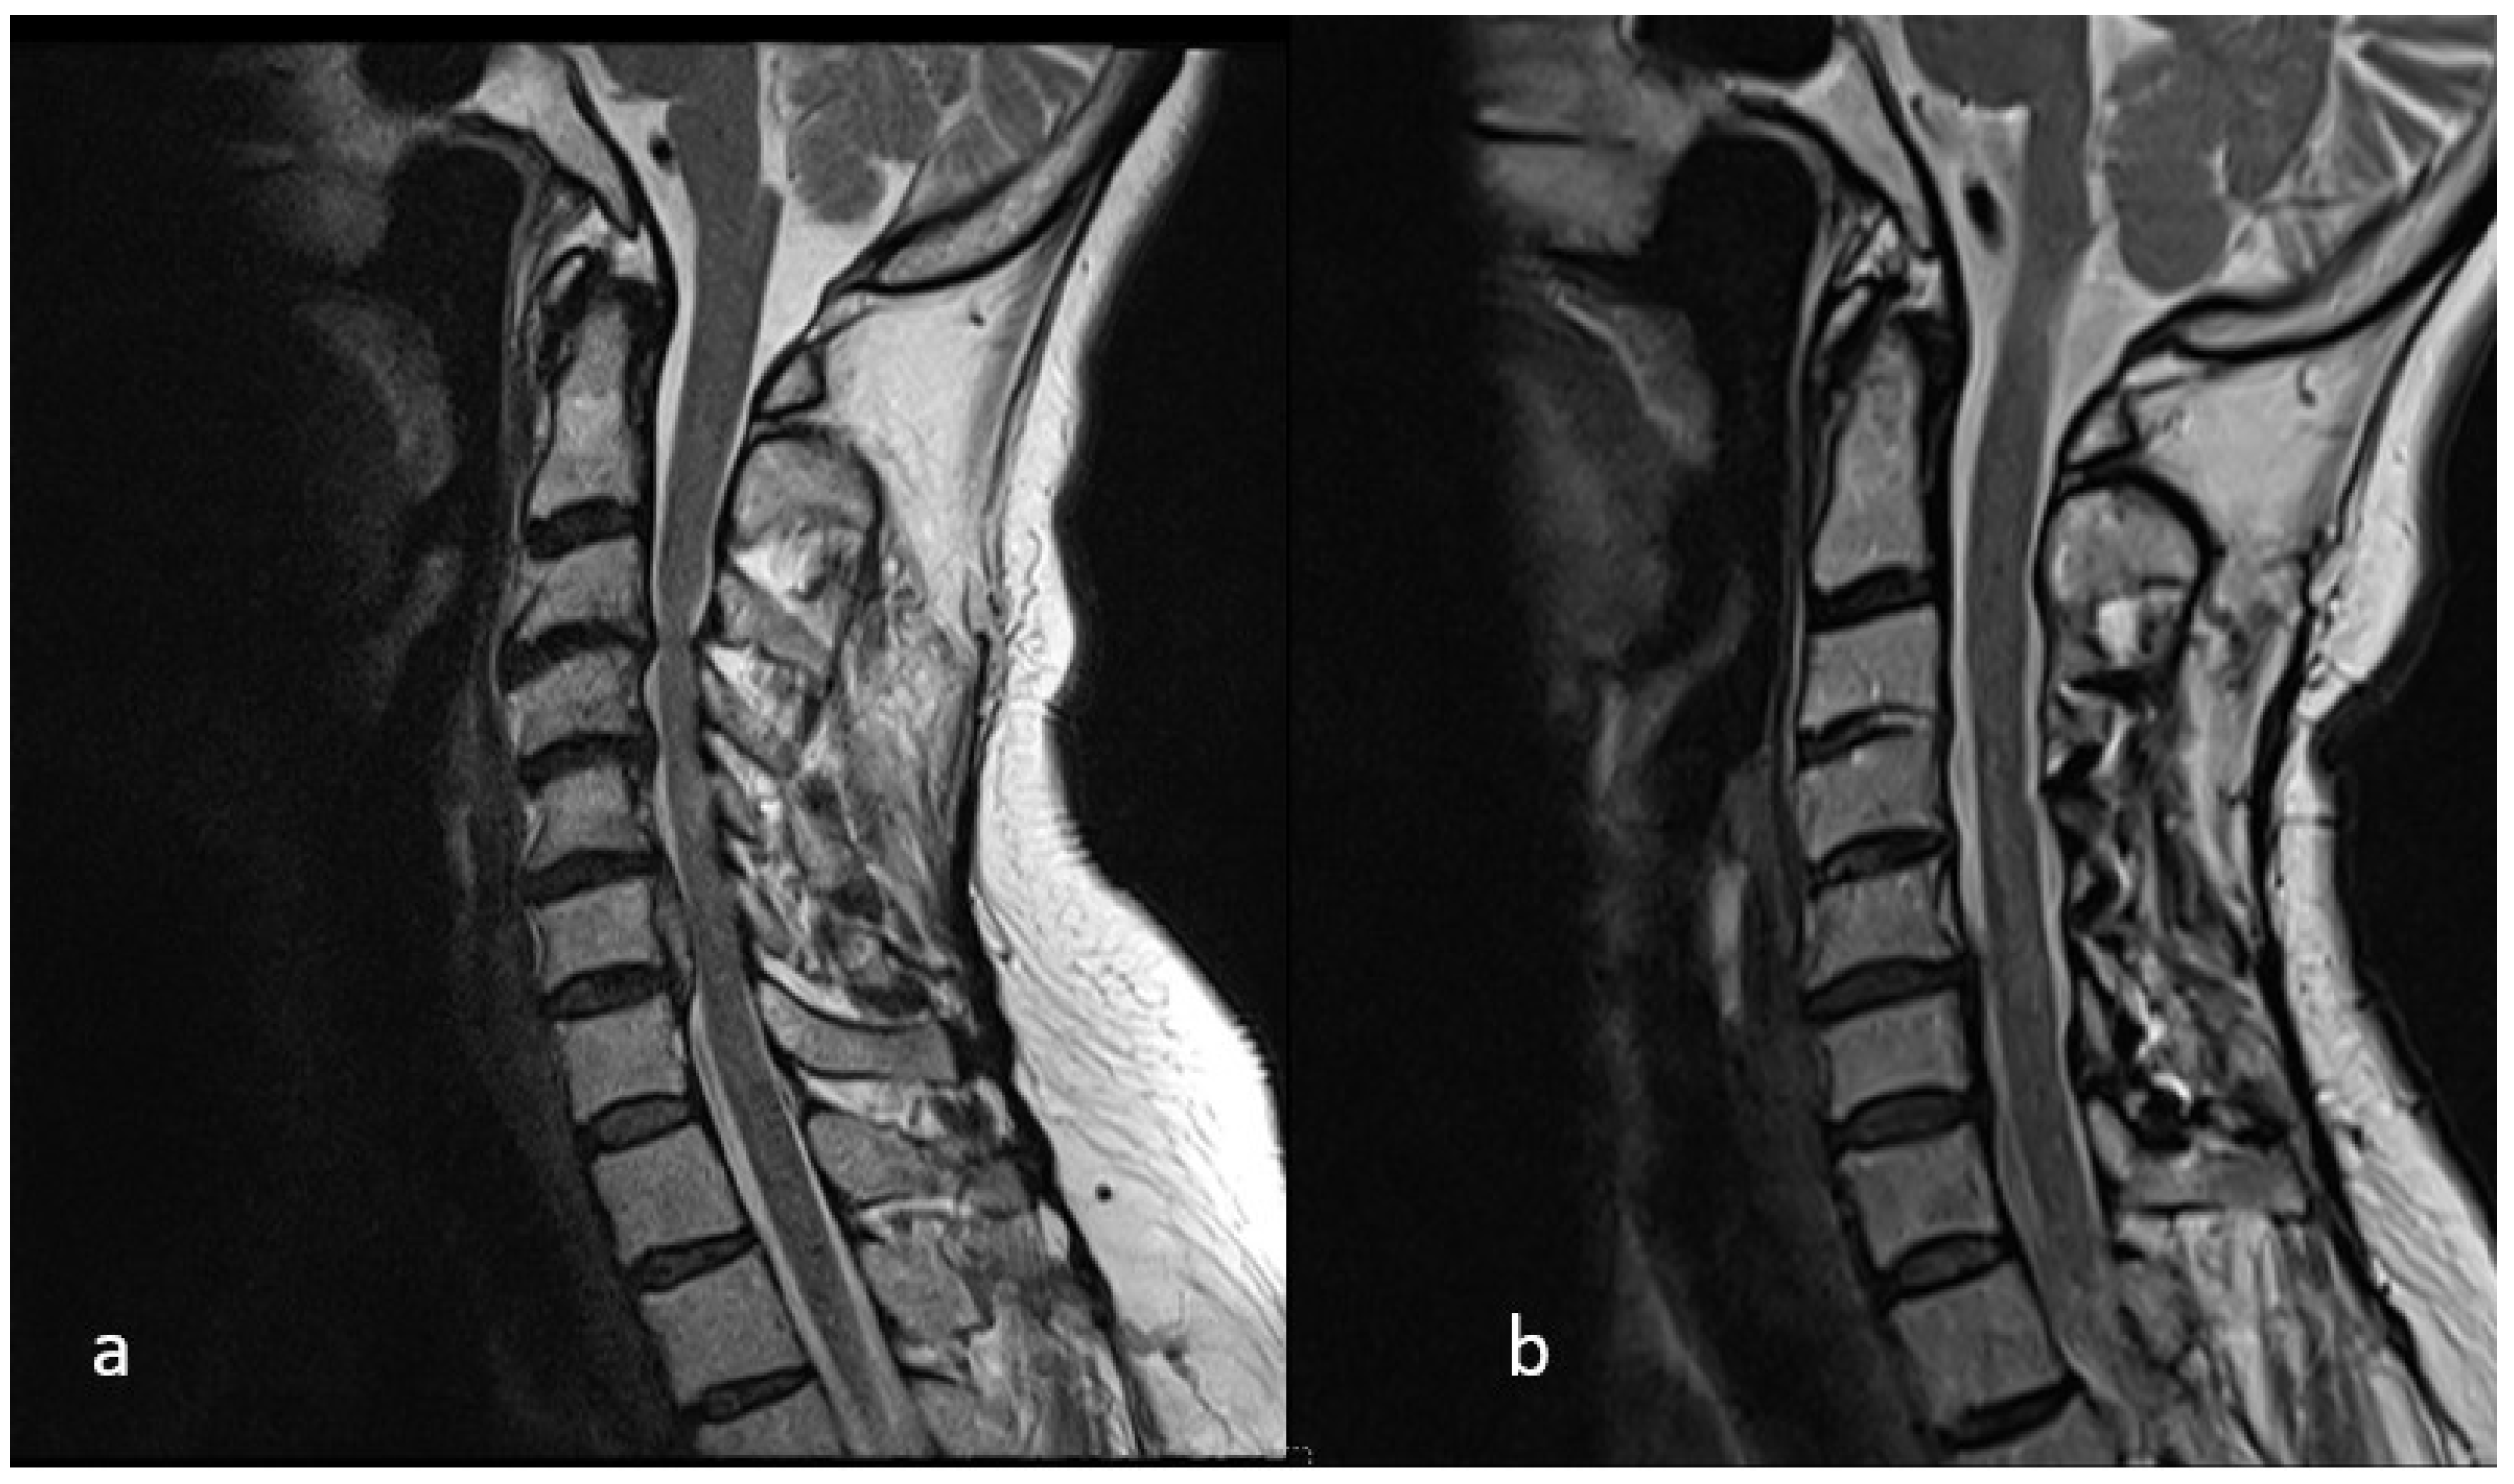

Preoperative Cervical Alignment Category vs. Postoperative Cervical Alignment Category

Preoperative K-Line vs. Postoperative K-Line